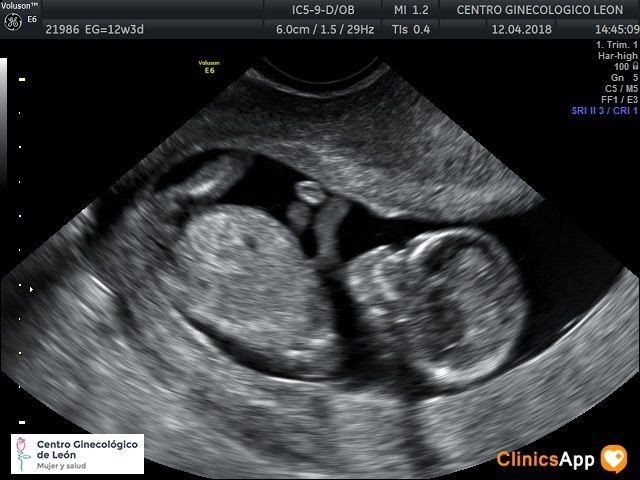

Ecografías del 12 de abril de 2018